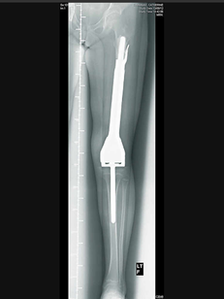

A Shropshire schoolgirl, who contracted a rare form of cancer, has been fitted with a metal leg bone which will "grow with her" as she gets older.

Hannah Baker, 9, from Clee St Margaret, had the femur in her left leg removed after she was diagnosed with an osteosarcoma tumour in April.

Surgeons at the Royal Orthopaedic Hospital in Birmingham, have replaced it with a special titanium rod which is extended by using electromagnetic pulses.

The titanium implant has motors inside it to allow it to be extended to match the length of Hannah's healthy leg.

The metal rod in Hannah's leg can be extended without surgery